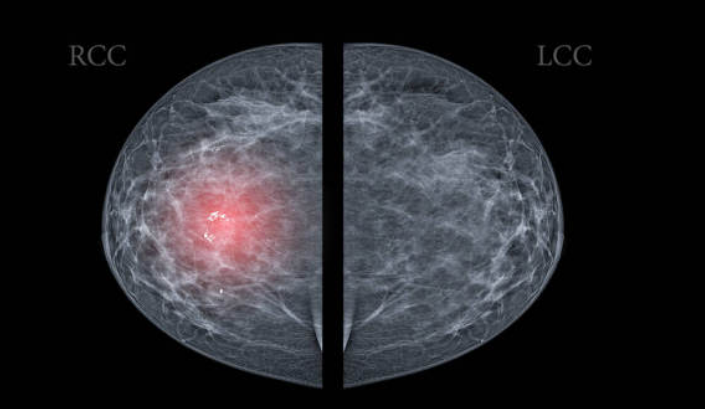

每年至少安排一次例行体检。性质不好的结节,在影像学上的风险特征都是微钙化、边界不规则、纵横比大于1、极低回声等。

一经查出此类结节且伴有腋窝、颈部淋巴结肿大,或红肿热痛、乳头溢血溢液等症状时,需尽快就医。